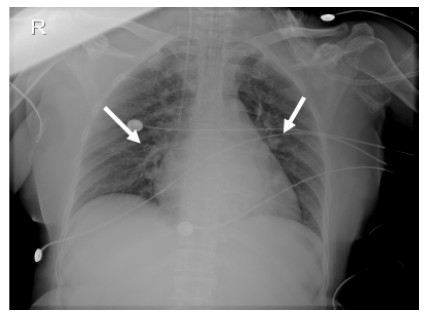

1 临床资料 1.1 病史摘要、体征及辅助检查患者51岁,中年女性,因吸入甲酸甲酯挥发气体后出现“恶心、呕吐,意识改变1h”于2021年6月12日1:30由120急诊送至我院。患者入院后0.5 h迅速出现意识改变,既往体健。入科时查体:体温35℃,脉搏129次/min,呼吸23次/min,血压114/44 mmHg(1 mmHg=0.133 kPa),指脉氧饱和度76%(吸氧状态下、氧流量8 L/min),颜面及四肢皮肤黏膜发绀,衣物上可见少量呕吐物,可闻及刺激性气味。神志恍惚,双侧瞳孔圆形等大、光反射敏感。对答基本切题。双肺呼吸音粗,可闻及少量湿性啰音。入院时胸部X片示:双肺斑片状渗出影(见图 1)。入院后约0.5 h出现意识丧失,立即行经口气管插管接呼吸机辅助呼吸同时建立中心静脉输液通道。辅助检查:白细胞13.11×109/L;中性粒细胞比率95.30%;降钙素原0.02 ng/mL;血生化:肌红蛋白 < 21.00 ng/mL、脑利钠肽前体497.6 pg/mL、丙氨酸氨基转移酶11.0U/L、天门冬氨酸氨基转移酶13.8 U/L、肌酐45 μmol/L、血钾3.37 mmol/L。心肌酶未见异常。动脉血气分析:pH 7.35,PO2 179 mmHg,PCO2 42 mmHg,lac 3.3 mmol/L,SPO2 100%(FiO2 100%)。中心静脉血气分析:pH 7.34,PO2 21 mmHg,PCO2 45 mmHg,ScvO2 31%,lac 2.9 mmol/L(FiO2 100%),经计算氧合指数小于200 mmHg,见图 2及附图1。

| 双肺散在小斑片状密度增高影、以双肺野中部显著 图 1 患者入院时胸部X片 |